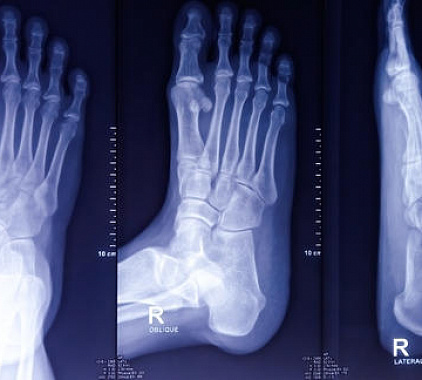

Чаще всего проводится рентген стопы в двух проекциях (боковой, прямой). Во время рентгена в прямой проекции человек лежит на спине. Ноги сгибает в коленях и ставит их на стол. При боковом рентгене стопы пациент ложится на бок. Пораженная конечность лежит на кассете. Иногда осуществляется рентген стопы в косой проекции. Человек лежит на спине. Ноги согнуты. Изучаемая конечность повернута на нужный угол.

Расшифровка результатов

Во время расшифровки результатов доктор изучает полученные изображения. Оценивает видимые структуры, сравнивает готовые данные с рентгеном стопы в норме. Доктор диагностирует разные нарушения. Определяет их протяженность, параметры, внешний вид, очертания, характер поражения и другие особенности. Специалист пишет детальное заключение. Указывает верные рекомендации.

Что видно на рентгене стопы?

Посредством рентгенограммы ступни выявляют:

- остеофиты;

- аномалии развития;

- артроз;

- признаки подагры;

- нарушение целостности костей;

- остеосклероз;

- вывихи;

- трещины;

- инородные предметы;

- остеопороз;

- плоскостопие;

- артрит;

- асептический некроз;

- гнойные процессы;

- опухоли (доброкачественные, злокачественные);

- очаги метастаз;

- косолапость;

- вальгусную деформацию первого пальца.